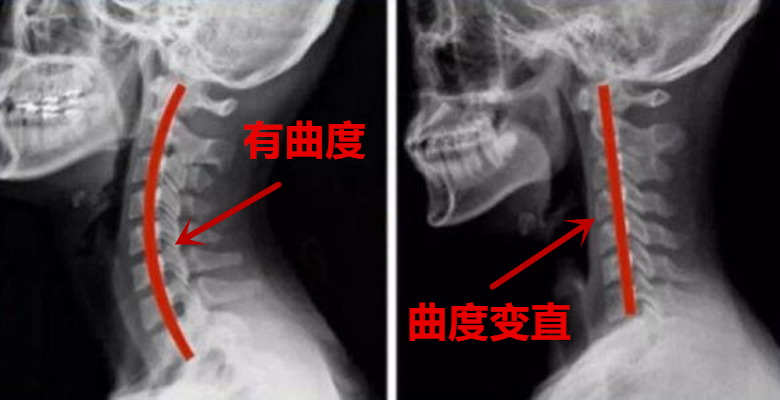

- 在X线片子上,颈型颈椎病可以没有明显的异常,但是也可以出现颈椎曲度变直、轻度骨质增生及椎间隙变窄的表现。

- 颈椎周围肌肉退变及劳损对骨骼的影响,颈椎曲度变直就是一个很好的佐证;